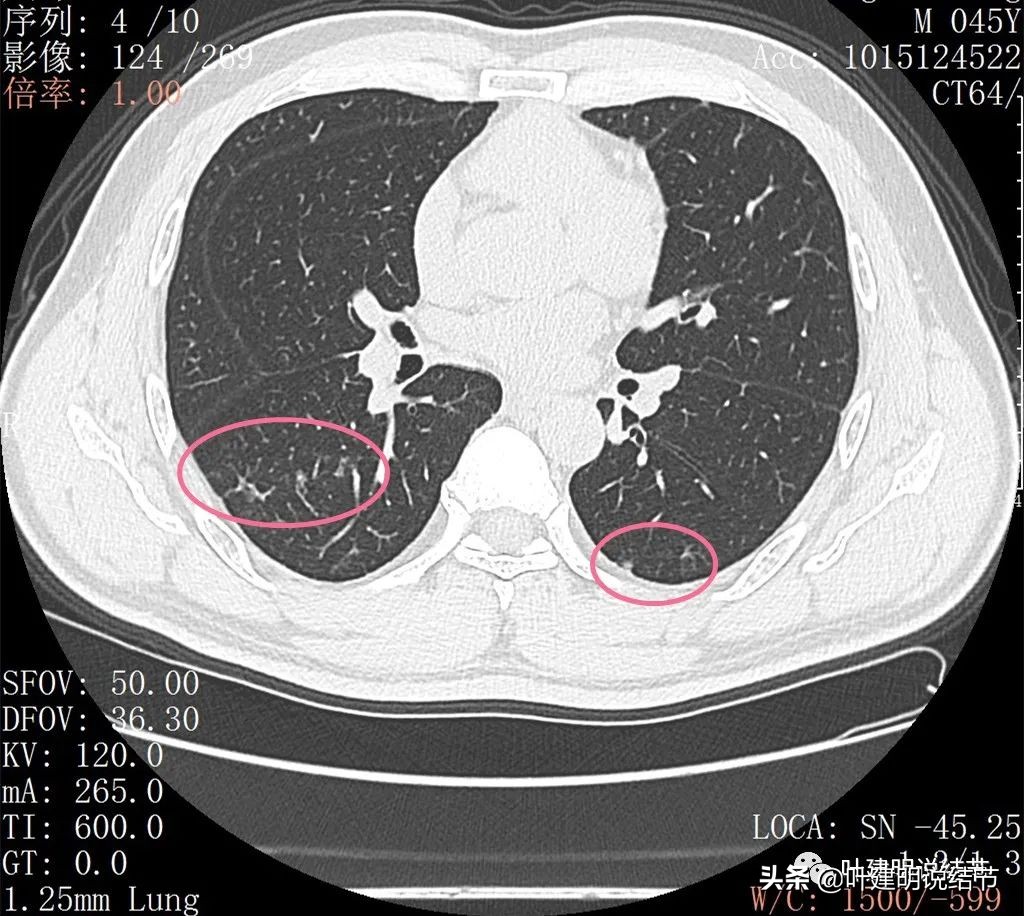

右下叶背段有散在斑点状病灶,形态类似,但较主病灶小得多;左侧也有小结节状。

邻近病灶的下叶背段处也有形态类似的病变